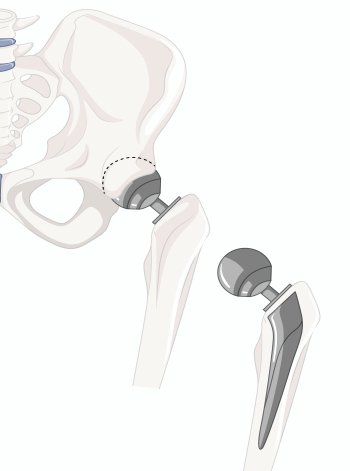

We are pleased to introduce Astha Hospital, the Best Multi-speciality Hospital in Chikali, offering world-class healthcare services to the communities of Moshi, Bhosari, and Pimpri Chinchwad, Pune. Our 50-bed, state-of-the-art tertiary care center provides comprehensive specialty and super-specialty treatments in Orthopaedics, Gynecology, Spine, Trauma, and Critical Care.